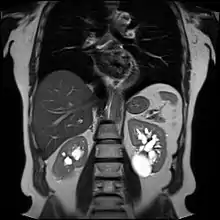

Advanced polycystic kidney disease with multiple cysts.[12]

Bosniak II cyst at the lower pole of right kidney with septations within.